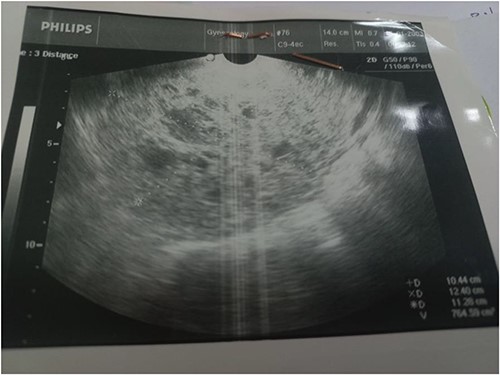

A 28-year-old female patient (G4B0) was admitted to the Department of Obstetrics and Gynecology with a history of severe pain in the right iliac fossa for several months, which had worsened for the last month. Physical examination revealed a large, palpable mass in the hypogastric region and the right lower abdominal quadrant. Vital signs, complete blood count, glucose, blood urea nitrogen, creatinine, alanine aminotransferase , aspartate aminotransferase, prothrombin time, activated partial thromboplastin time, and alpha-fetoprotein, were within normal limits. However, the CA-125 level was elevated at 52.8 U/mL. The vaginal US showed an unclear mass on the right side of the uterus with a similar appearance to a hydatidiform mole (Fig. 1). A pelvic CT scan with contrast showed a heterogeneous mass of 14 × 10 cm on the right side, containing several cystic vesicles lying in front of the uterus and displacing it posteriorly. There was no free fluid in the abdomen or pelvis. The patient’s condition deteriorated after 3 days, and she developed abdominal distension and mild tenderness. Surgery was performed, during which the entire mass was resected from the right ovary (Fig. 2). Histopathological examination revealed a follicular thyroid tumor originating from the right ovary (Fig. 3). Postoperative vital signs were within normal limits. The postoperative blood analyses were Hb = 9.7 g/dL, hematocrit (HCT): 28.5%, WBC: 10.4 × 10^9/L, neutrophils: 88%, and PLT: 182 × 10^9/L. Two units of blood were transfused, and the Hb level increased to 10.2 g/dL. Thyroid function tests, including thyroid-stimulating hormone and free thyroxine (FT4), were within normal limits. The patient was discharged in good condition after 5 days.